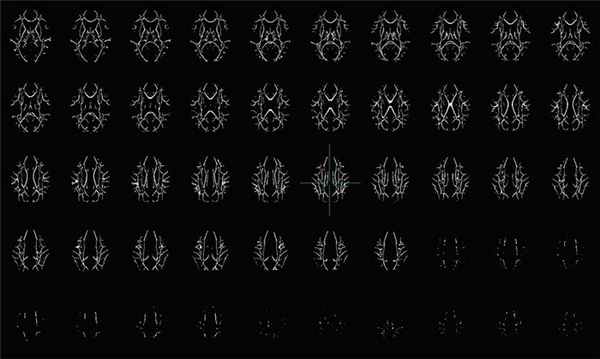

25 апреля 2018 года были опубликованы результаты клинического исследования, согласно которому МРТ-сканирование с использованием диффузионно-тензорной методики визуализации (DTI) способно выявить микроструктурные изменения в белом веществе головного мозга у людей, употребляющих кокаин.

Результаты исследований также дают новое представление о потенциальных периферических маркерах нейронального повреждения, а также о роли оксидативного стресса в изменении структуры нейронов и нарушении коэффициента водной диффузии.

Осевая проекция участков белого вещества в мозге. Исследователи использовали компьютерный анализ для определения статистических значимых различий между пациентами, имеющими нарушения в связи с употреблением кокаина, и здоровыми людьми

С помощью DTI и этих периферические маркеров окислительного стресса повреждение можно выявить задолго до развития клинической симптоматики психиатрического заболевания. Злоупотребление кокаином ведет к поражению белого вещества и изменениям микроструктуры во многих областях головного мозга. Наиболее уязвимой структурой оказалось мозолистое тело – эта подкорковая область связана с двигательной, сенсорной и когнитивной сферой деятельности мозга; кроме того, она интегрирует функции обеих полушарий.

Прошлые исследования показали, что изменения белого вещества при употреблении кокаина и других неврологических расстройствах могут быть связаны с оксидативным стрессом. Именно степень поражения при оксидативном стрессе позволяет определить DTI – эта методика визуализирует изменения в микроструктуре белого вещества на основе диффузии молекул воды.

В нормально миелинизированных аксонах осевая диффузия выше, чем радиальная, потому что поток воды движется по аксону к телу нейрона, а толстый миелиновый слой в норме предотвращает радиальную диффузию. При остром повреждении аксонов осевая диффузия уменьшается из-за фрагментации аксона; при хроническом повреждении происходит общее нарушение структуры нейронов и увеличение как осевой, так и радиальной диффузии.